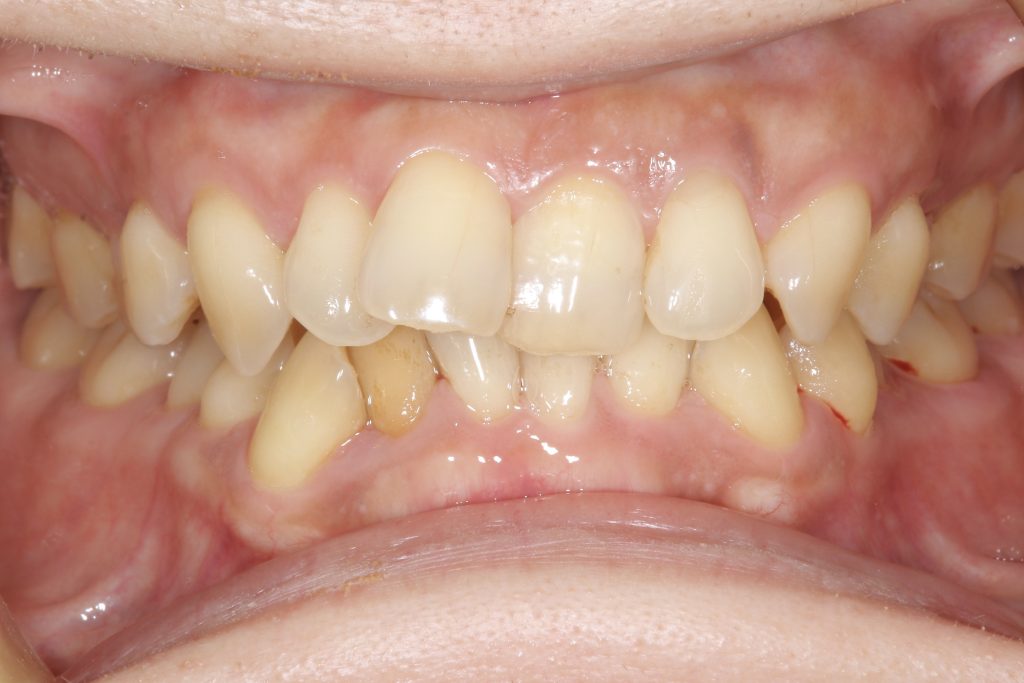

受け口の状態により、上の歯が内側に入り込み、反対の噛み合わせになっている部分が見られました。見た目の問題だけでなく、噛み合わせのバランスにも影響を与えていました。

- 前歯部交叉咬合を伴う不正咬合

- ゴムメタルワイヤー矯正

- 2024年9月6日(10ヶ月)